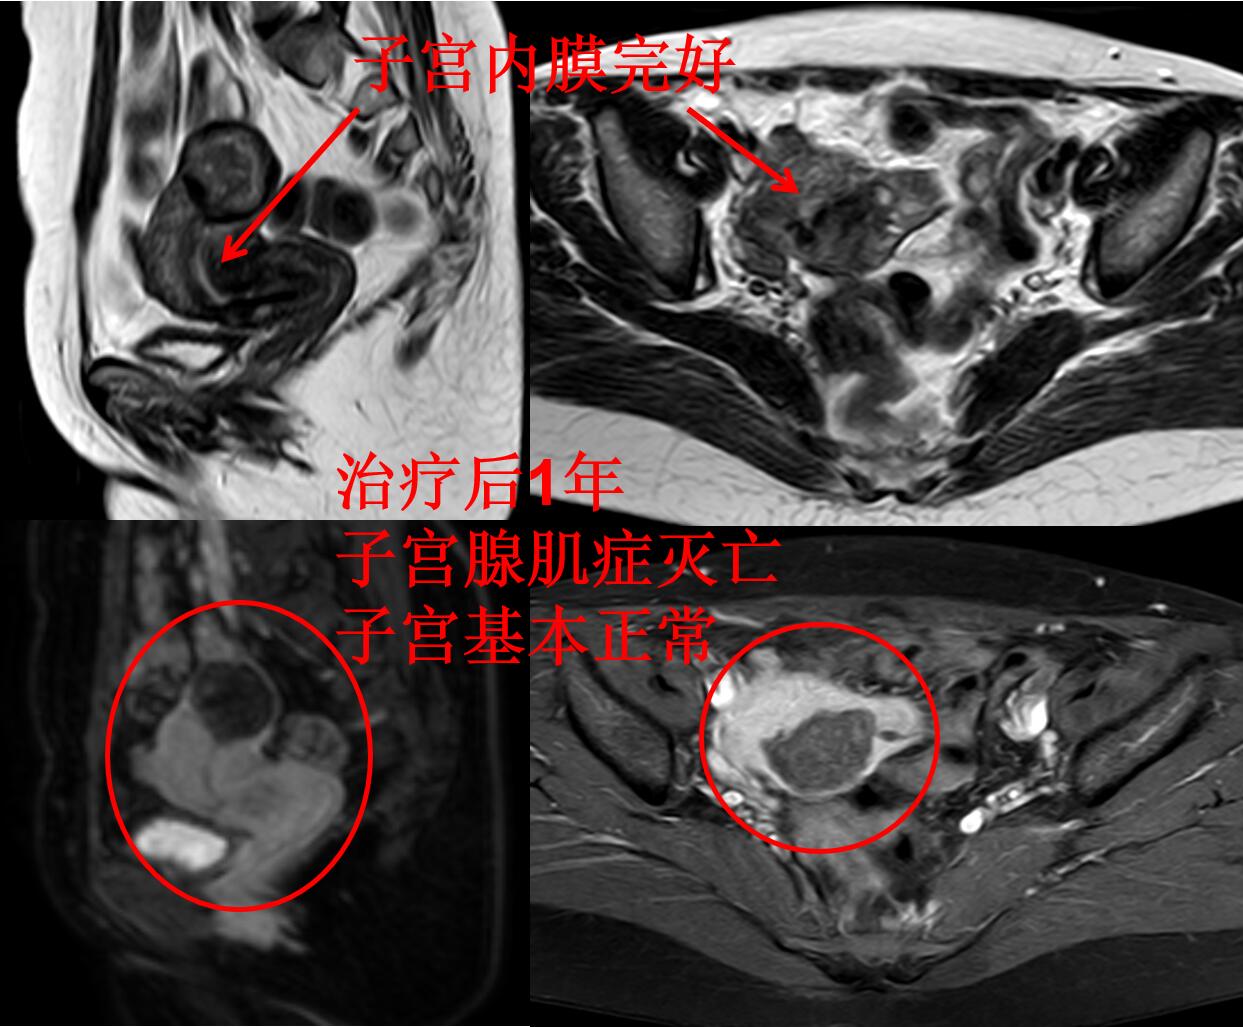

李女士治疗后满1年,痛经没有复发。下图为治疗后1年复查的磁共振图(子宫腺肌症完全灭亡,子宫基本正常(与没有腺肌症的正常妇女的子宫相仿))。